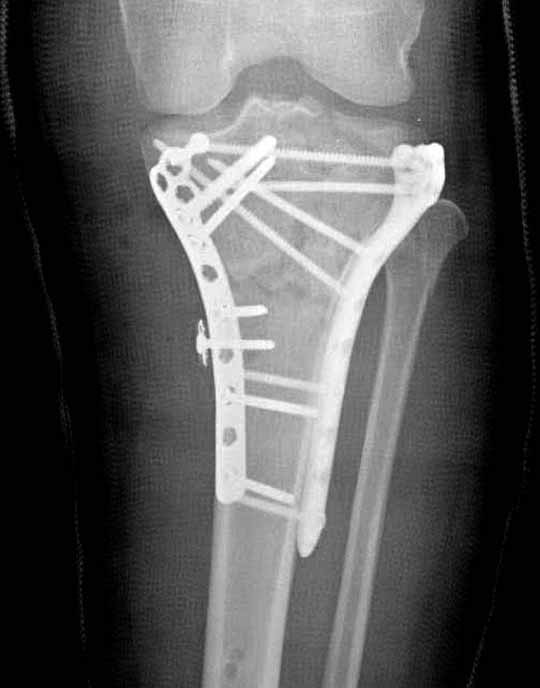

В приложении этапы фиксации Both Column Fx и пластиной Synthes для плеча при переломе медиального мыщелка.

Частая ошибка, когда фиксацию двух колонного перелома проводят одиночной пластиной, т.е с одной стороны, и такая фиксация не удерживает, происходит вторичноое смещение. Необходимо нейтрализовать второй пластиной или дополнительным наружным фиксатором.

Если у вас, кроме пластины, нет другого альтернативного варианта, тогда, учитывая мягкотканые проблемы с наружной стороны, я бы рекомендовал операцию делать в два этапа. Преимущества, сперва репозиция и фиксация перелома с медиальной стороны, а затем, после улучшения состояния мягких тканей, зафиксировать с латеральной стороны. Современные пластины имеют латеральный Jig для перкутанных мини доступов.

В основном пластины рассчитаны на латеральную поверхность, потому что с латеральной стороны больше мягкотканая подушка, а также через латеральную колонну проходит ось конечности, что немаловажно в удержании оси от деформации.

Для изолированных переломов медиального тибиал плато, фиксацию можно провести “медиальной пластиной”. Некоторые компании, например Smith & Nephew делают медиальные и медиально-задние пластины, но они мягкие, и легко можно создать нужный контур. Жесткость создается за счет фиксации жесткими пластинами, например экстра артикулярной пластиной для дистального плеча от Synthes. Медиальный доступ тоже не из легких, надо работать между pes and medial gastroc.